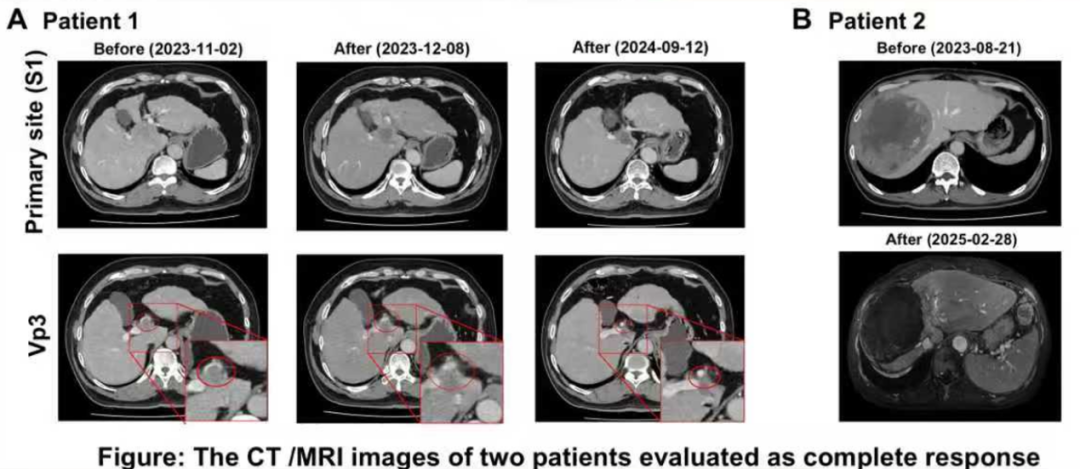

疗效评估:客观缓解率(ORR)达到85.7%(6/7),其中治疗区域的ORR更是高达100%。具体而言,完全缓解(CR)率为28.6%(2/7),这两例患者的CR状态持续了9个月;部分缓解(PR)率为57.1%(4/7)。仅1例患者(14.3%)出现疾病进展(PD)。

两例被评估为完全缓解患者的CT/MRI图像

安全性评估:没有患者出现3级及以上不良事件(AE)。最常见的不良事件是腹痛和呕吐,且所有并发症均可控。

90Y-SIRT联合Atezo-Bev治疗uHCC,展现出令人鼓舞的局部ORR(100%)和良好的安全性。这些初步发现有待未来在更大样本量的队列中进一步验证,以明确该联合方案的最佳治疗顺序及治疗时长,为临床实践提供更可靠的循证依据。

本研究初步探讨了90Y-SIRT和Atezo-Bev联合疗法在中国患者队列中的疗效和安全性。当前数据表明,该联合治疗方案在局部肿瘤控制方面表现出显著效果,局部ORR达到100%,结果令人鼓舞,同时安全性良好。上述结果表明,90Y-SIRT联合Atezo-Bev可能是晚期HCC的一种有前景的治疗选择。放射治疗引起的细胞改变是随时间动态变化的,需要进一步明确该联合方案的最佳治疗顺序及治疗时长等。未来有待通过大样本随机对照研究来明确最佳用法、适合人群和远期生存获益。